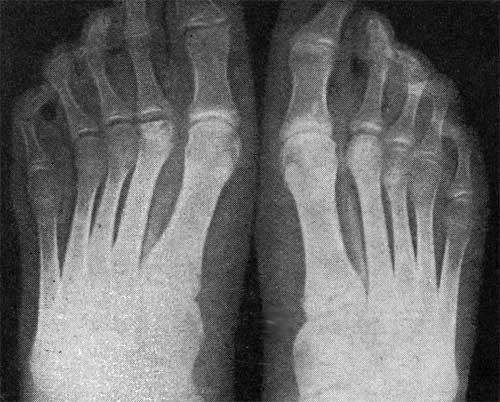

Болезнь Келлера Фото

Болезнь Келлера Фото 145 фотографий